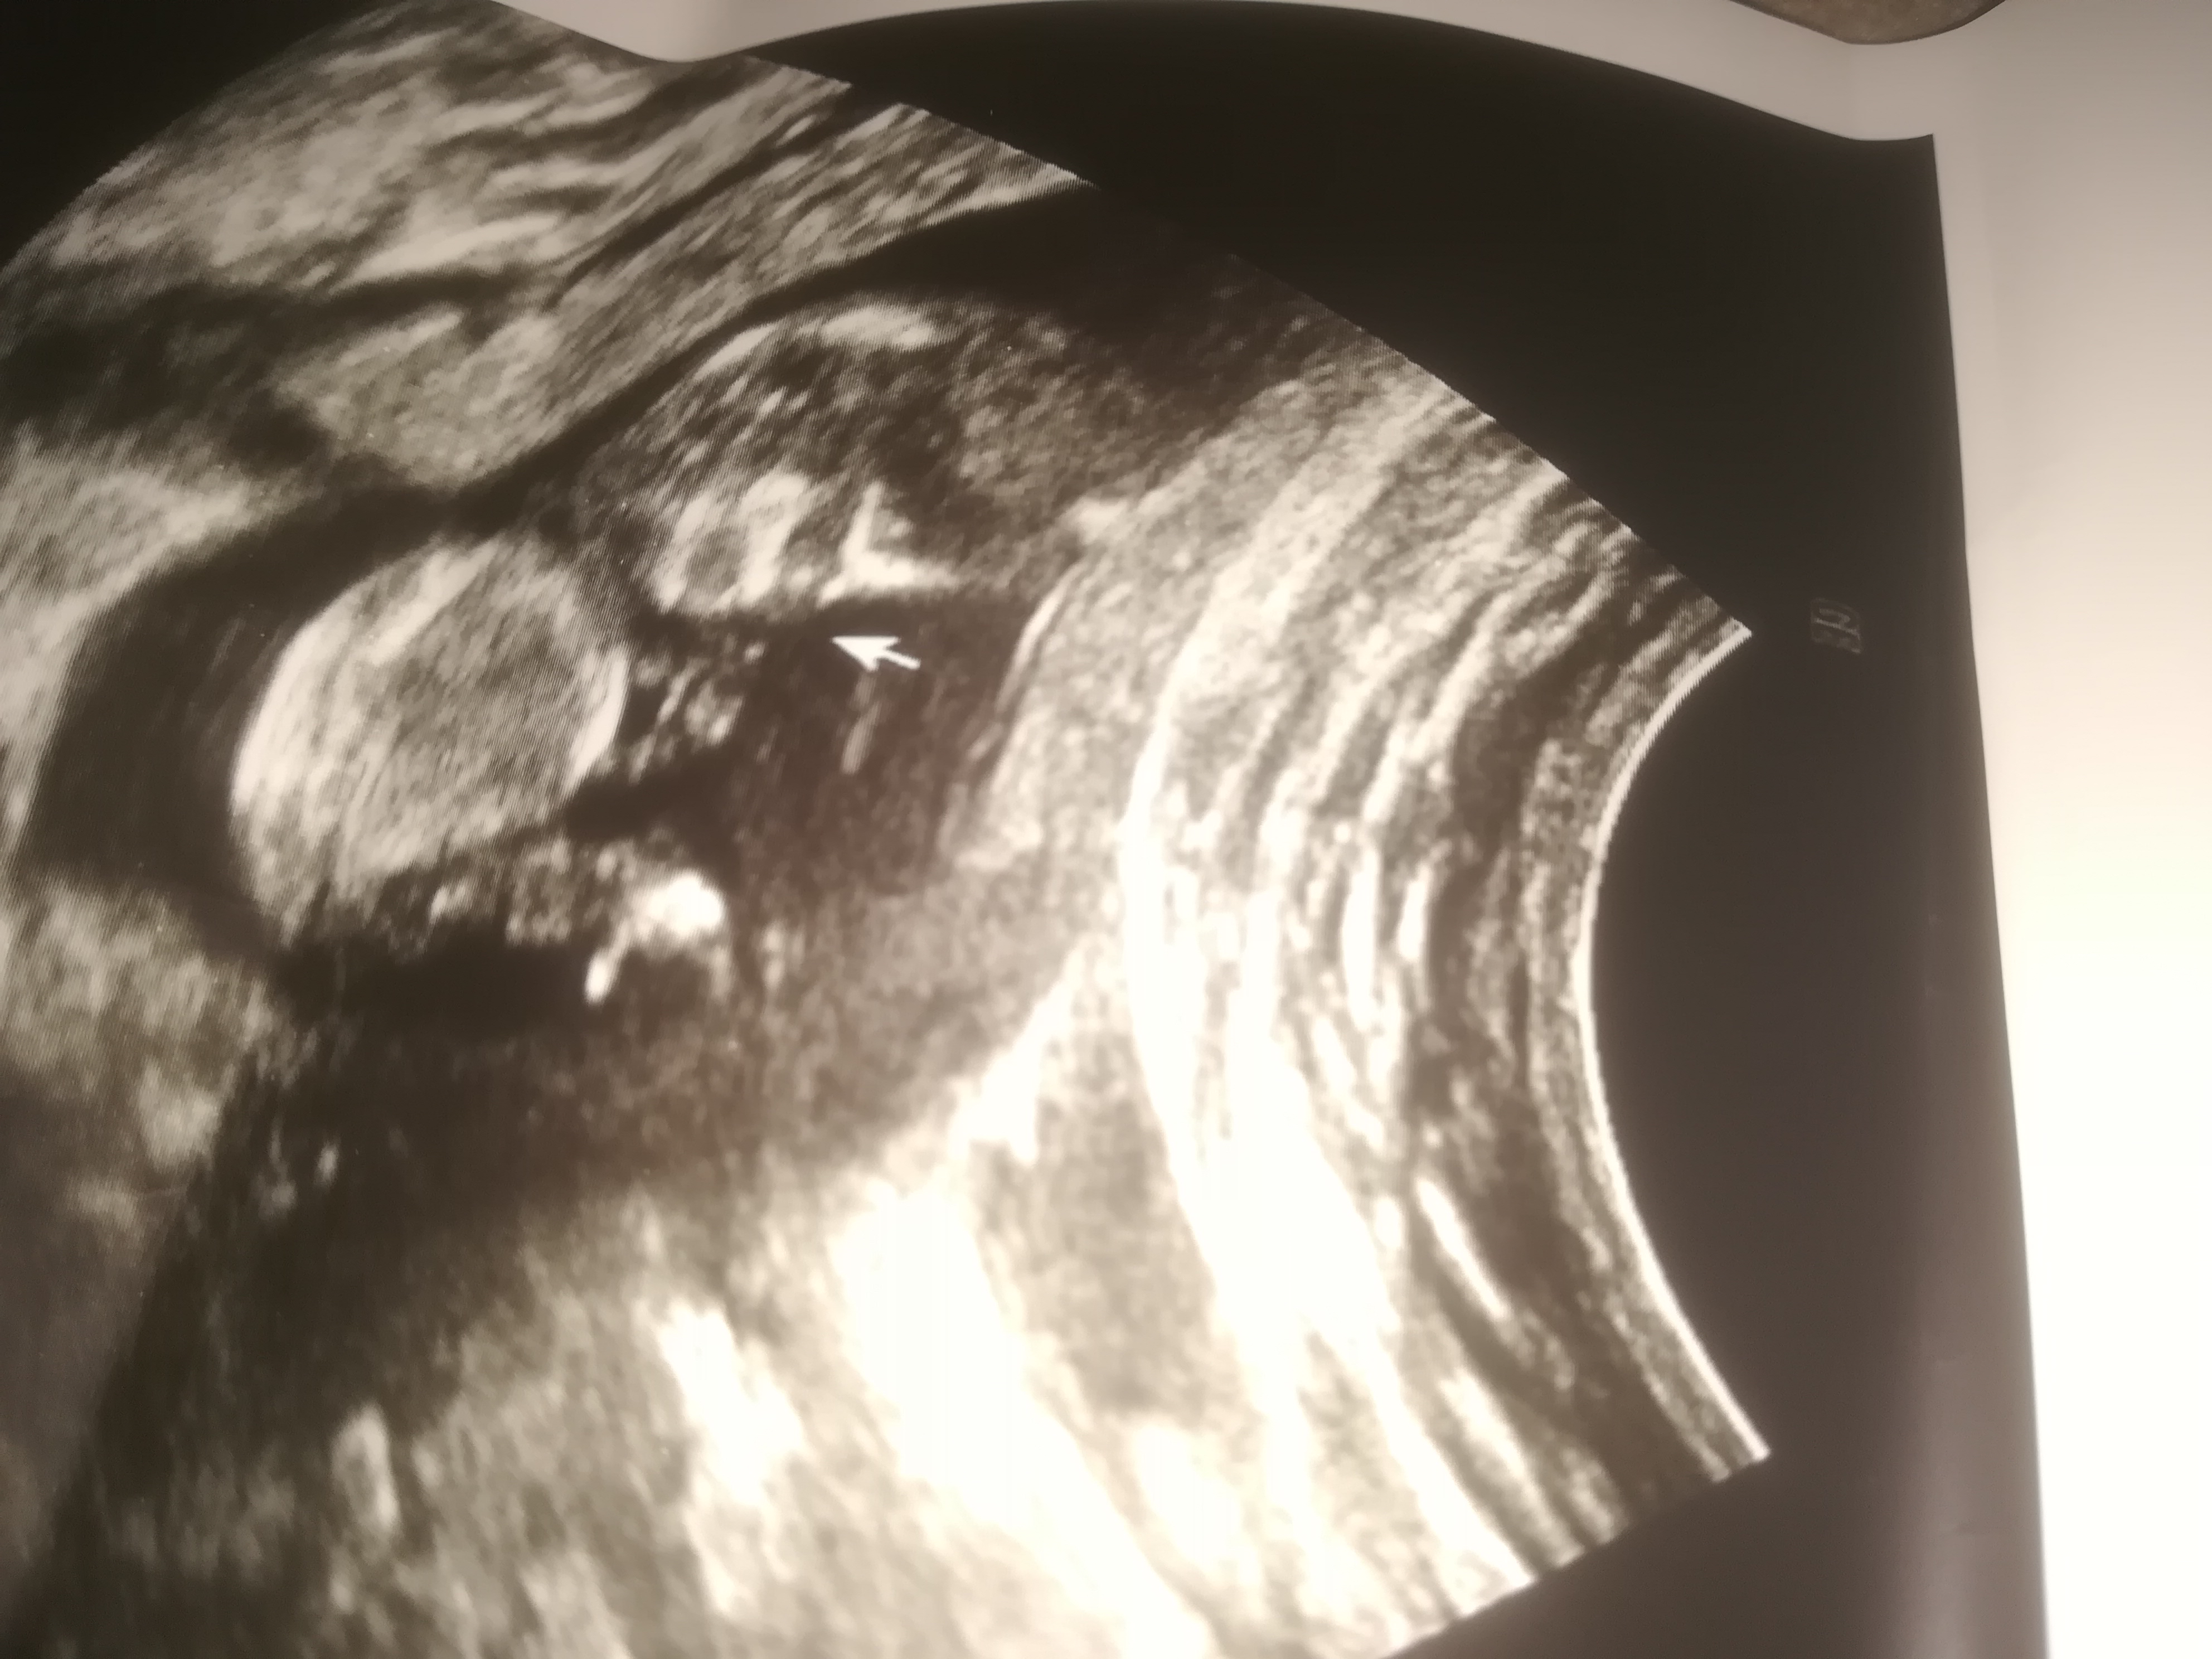

Bizlere ulaşan sevgili Ezgi kardeşimizin gönderdiği resmi ekliyorum meleklerim. Sizler de info@meleklermekani.com adresine ultrason resimlerinizi gönderebilirsiniz. Resimler net olsa iyi olur. Sevgili Ezgi tam istediğimiz netlikte değil hayatım ama bebeğinin Erkek olacağını düşünüyorum. Yüzde yüz budur diyebilseydim keşke ama çıkıntıyı gördüğümü düşünüyorum. Hayırlı olsun hayatım.

nub cinsiyet tahmini ezgi dolanbay.jpg

Daha başka resim var ise özellikle çıkıntının olduğu bölümü atabilirsen daha net sonuç verebiliriz.

Sevgili Ezgi, evet mail ile ulaşmışsın bizlere ama soru cevapları bu konu üzerinden devam ettirelim ki sizin durumunuzda olup bebeğinin cinsiyetini merak eden anne adaylarına da ışık olsun. Dediğiniz gibi ben o çıkıntıyı acaba kordon mu diye düşündüm ama iyice inceleyip büyütünce çıkıntıya göre şimdi erkek diyebiliyorum. Hayırlısı bakalım 🙂